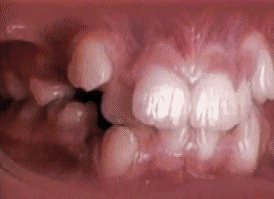

矯正牙齒

原理:這張動圖展示了牙齒矯正的過程,原視頻整個經曆的時間跨度為18個月。牙齒矯正器會對牙齒施加適當的壓力,在成骨細胞和破骨細胞的作用下,牙槽骨逐漸被重塑,進而使牙齒排列整齊。

花絮:與我們的祖先相比,現代人類的頜骨寬度減小、長度縮短,可供牙齒萌出的空間也隨之變小,這使得我們麵臨了更多的牙齒排列問題,在智齒上這一點尤為明顯。